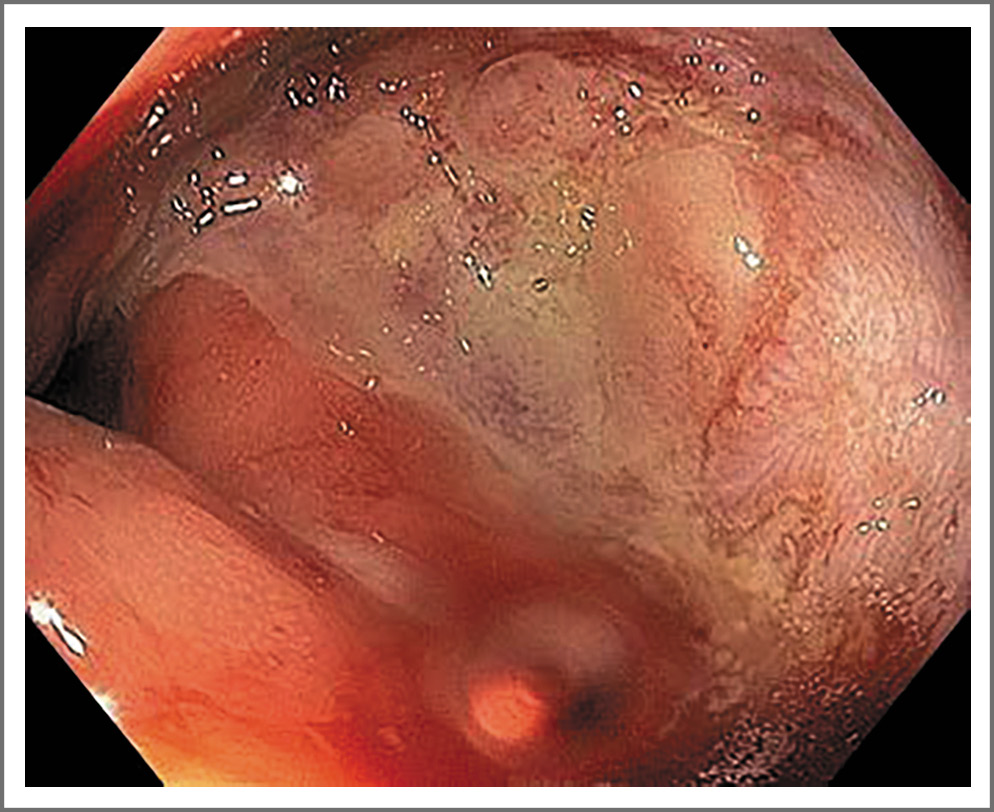

С момента реконструктивной операции ухудшений самочувствия пациент не отмечал. Стул ежедневный, оформленный, 4-й тип по Бристольской шкале без патологических примесей, болевого синдрома при дефекации нет. Поддерживающая противорецидивная терапия ЛП: месалазин (Салофальк) в дозе 2 г/сут перорально в виде гранул, ректальная терапия выходного дня – клизмы/пена месалазин (Салофальк) 2 г/сут, двухмесячные курсы препарата масляной кислоты (Закофальк) 750 мг/сут. Контрольную ректороманоскопию провели спустя 1 год после реконструктивной операции и 3 года после некроза стенки прямой кишки – некротический дефект по передней брюшной стенке до 1/3 диаметра выполнен соединительной тканью (рис. 5), слизистая ампулы прямой кишки с единичными телеангиэктазиями (рис. 6), без спонтанной кровоточивости, незначительная контактная кровоточивость на границе с фиброзной тканью по левой стенке. По результатам эндоскопического осмотра – ЛП в стадии ремиссии.

Рис. 5. Колоноскопия от 23 марта 2023 г. Соединительнотканный дефект прямой кишки.

Fig. 5. Colonoscopy, March 23, 2023. Connective tissue defect of the rectum.

Рис. 6. Колоноскопия от 23 марта 2023 г. Единичные телеангиэктазии прямой кишки.

Fig. 6. Colonoscopy, March 23, 2023. Single telangiectasia of the rectum.